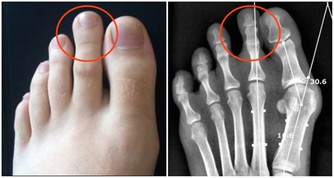

3、突然出現一過性半身麻木乏力,以手足部位最為突出。

這些症狀是頸內動脈系統短暫腦缺血發作所致,從而影響了偏側肢體活動的感覺和運動功能。